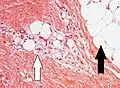

Lipoblast features.

Lipoblasts are seen in liposarcoma[7] and characteristically have abundant multivacuolated clear cytoplasm and a dark staining (hyperchromatic), indented nucleus.